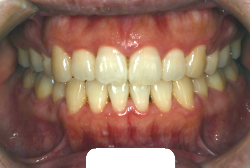

「歯並びの凸凹を直したい」という主訴で来院したケースです。診断の結果、たしかに「叢生」という隙間が足りないと言うことが原因の凸凹症例でした。

しかし、それ以上に問題なのは「前歯の噛み合い方が深すぎる」という症状で、初診の歯の正面写真を見ると下の前歯が全く見えません。こういう症状を矯正学では「過蓋咬合(かがいこうごう)」と言います。過蓋咬合を放置すると、将来的に顎関節に悪影響を与えるとされており、顎関節症の原因因子の一つです。また下の前歯の先端が、上の前歯の裏側の歯茎と強く接触するため、歯周病の原因にもなります。

検査の結果、凸凹が軽症なため非抜歯で矯正すること可能と判断、マルチブラケット装置にて治療しました。治療後は歯並びが綺麗になっただけでなく、噛み合わせ的にも正しい状態が確立しています。